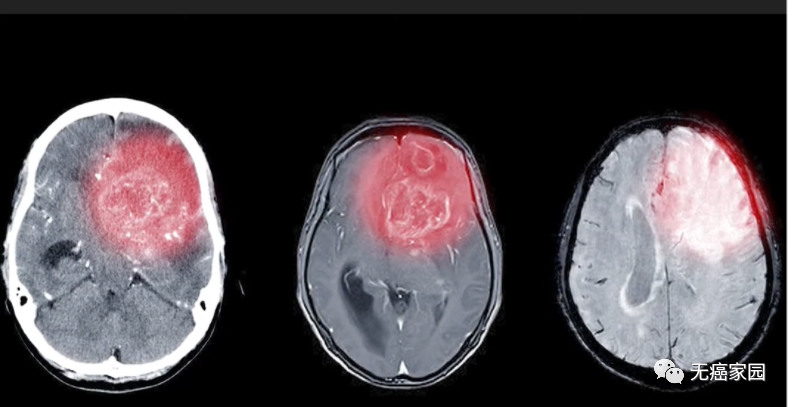

2、胶质母细胞瘤——AV-GBM-1疫苗

据国外研究报道,原发性胶质母细胞瘤患者的标准治疗方法与不良的预后有关。研究人员推测,使用针对患者的疫苗进行辅助治疗可以通过增强免疫反应来帮助改善患者的预后。

2021年6月8日,国外知名生物医学公司宣布其个性化癌症疫苗AV-GBM-1的II期临床试验数据公布,研究显示此款新型疫苗对延长新诊断的胶质母细胞瘤患者的中期总体生存期展现出极大的潜力。

该试验纳入的57例患者在6个月内接受8剂AV-GBM-1疫苗,在分析时,存活患者已完成治疗,并在入组后10.1~27.6个月内进行随访,中位无进展生存期为10.4个月,与具有里程碑意义的STUPP研究中的中位无进展生存期6.9个月相比,提高了约50%,为新诊断的胶质母细胞瘤患者建立了护理标准。

这表明在6.9个月时进展或死亡的风险降低了42%。中位生存期尚未达到,将在最终患者至少随访15个月后进行评估。

总体而言,患者的治疗耐受性良好,发生的所有不良事件均与疫苗无关。